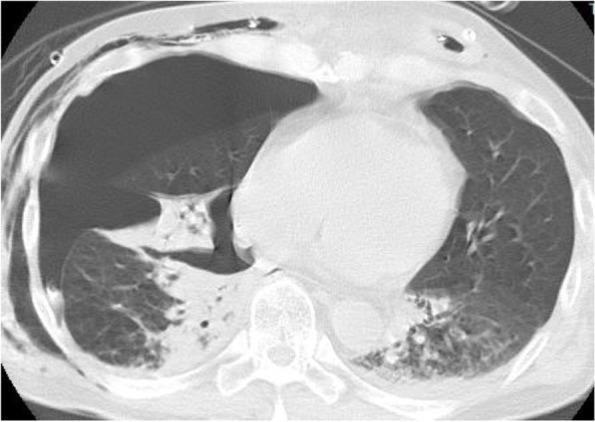

A 56-year-old man underwent video-assisted thoracic surgery for esophageal cancer. The right lung was injured during surgery, causing a bronchopleural fistula and necessitating chest drainage. On the third day in the intensive care unit, the patient's oxygenation worsened during pressure support with continuous positive airway pressure ventilation. ILV was initiated for right-sided severe pneumothorax and left-sided atelectasis and pneumonia. ILV was continued for 2 days, and the patient's trachea was successfully extubated the following day.